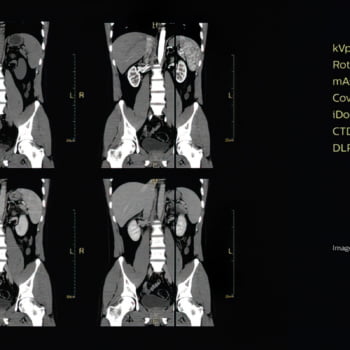

Veja mais detalhes em uma grande variedade de pacientes

Proporciona uma qualidade de imagem excepcional mesmo para pacientes pequenos

O modo de varredura de 70 kV – o primeiro em um sistema de seu tipo – ajuda a levar o cuidado do paciente a um novo nível, oferecendo escaneamento em baixas doses de pacientes menores e permitindo a proteção de órgãos sensíveis à radiação. Este modo de varredura oferece até 20% de escaneamento em doses mais baixas do que 80 kV.